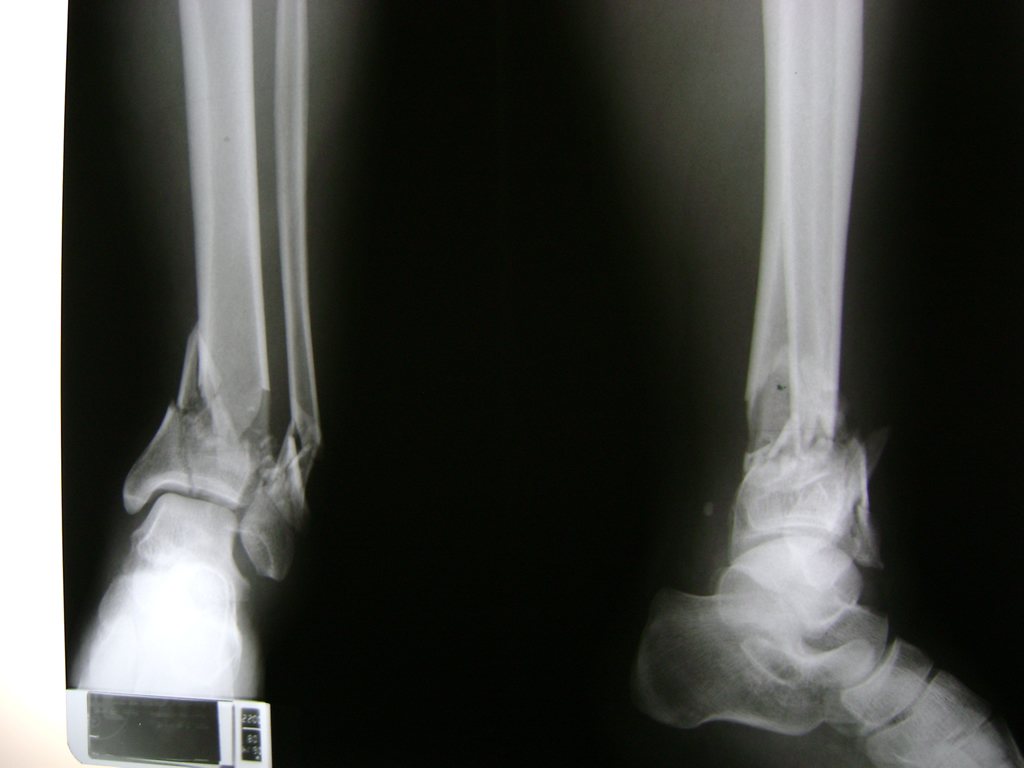

Una fractura de tobillo es la rotura de uno o más de los huesos del tobillo. Estas fracturas pueden ser:

- Parciales (el hueso está sólo parcialmente fisurado, no del todo).

- Completas (el hueso está perforado y está en 2 partes).

- Producirse en uno o ambos lados del tobillo.

- Los extremos de los huesos están desalineados entre sí (desplazados).

- La fractura se extiende hasta la articulación del tobillo (fractura intra-articular).